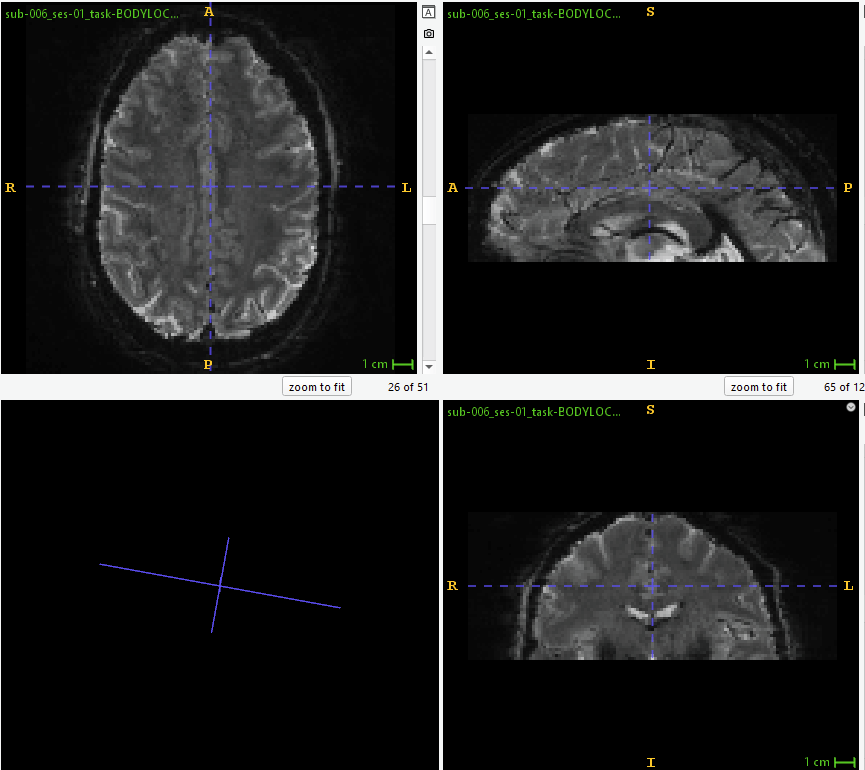

See below for a screenshot from sub_ses_task-task_run-1_desc-coreg_boldref.nii (for reference, how the EPI looks without signal stretched outside of FoV; using ITK Snap 4.2.2):